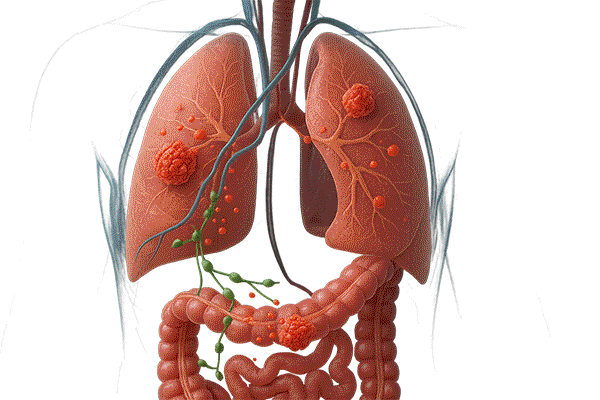

■ (転移 ステージⅣ) 転移が起こる

・特に大腸がんは肝臓や肺に転移しやすい性質があります。

■ 転移しやすい臓器

大腸からの血流は門脈を通じて肝へ集まるため、肝転移が起こりやすいと考えられ、特に 肝臓や肺 に転移しやすいがんです。

・肝臓転移:大腸の血流は門脈を通じて肝臓に流れ込むため、がん細胞が血液に乗って肝臓に到達しやすい。

・肺転移:血流に乗ったがん細胞が肺の毛細血管にとどまり、そこで増殖することがあります。

■ 転移のメカニズム

● 大腸のがん細胞が腸壁を破って血管・リンパ管に入り込む

● 血液やリンパの流れに乗って全身へ運ばれる

● 肝臓や肺などに到達し、新しい腫瘍(転移巣)をつくる。この「転移巣」は、元の大腸がんと同じ性質を持つため、大腸がんが肝臓に転移した場合でも「肝臓がん」ではなく「大腸がんの肝転移」と呼びます。